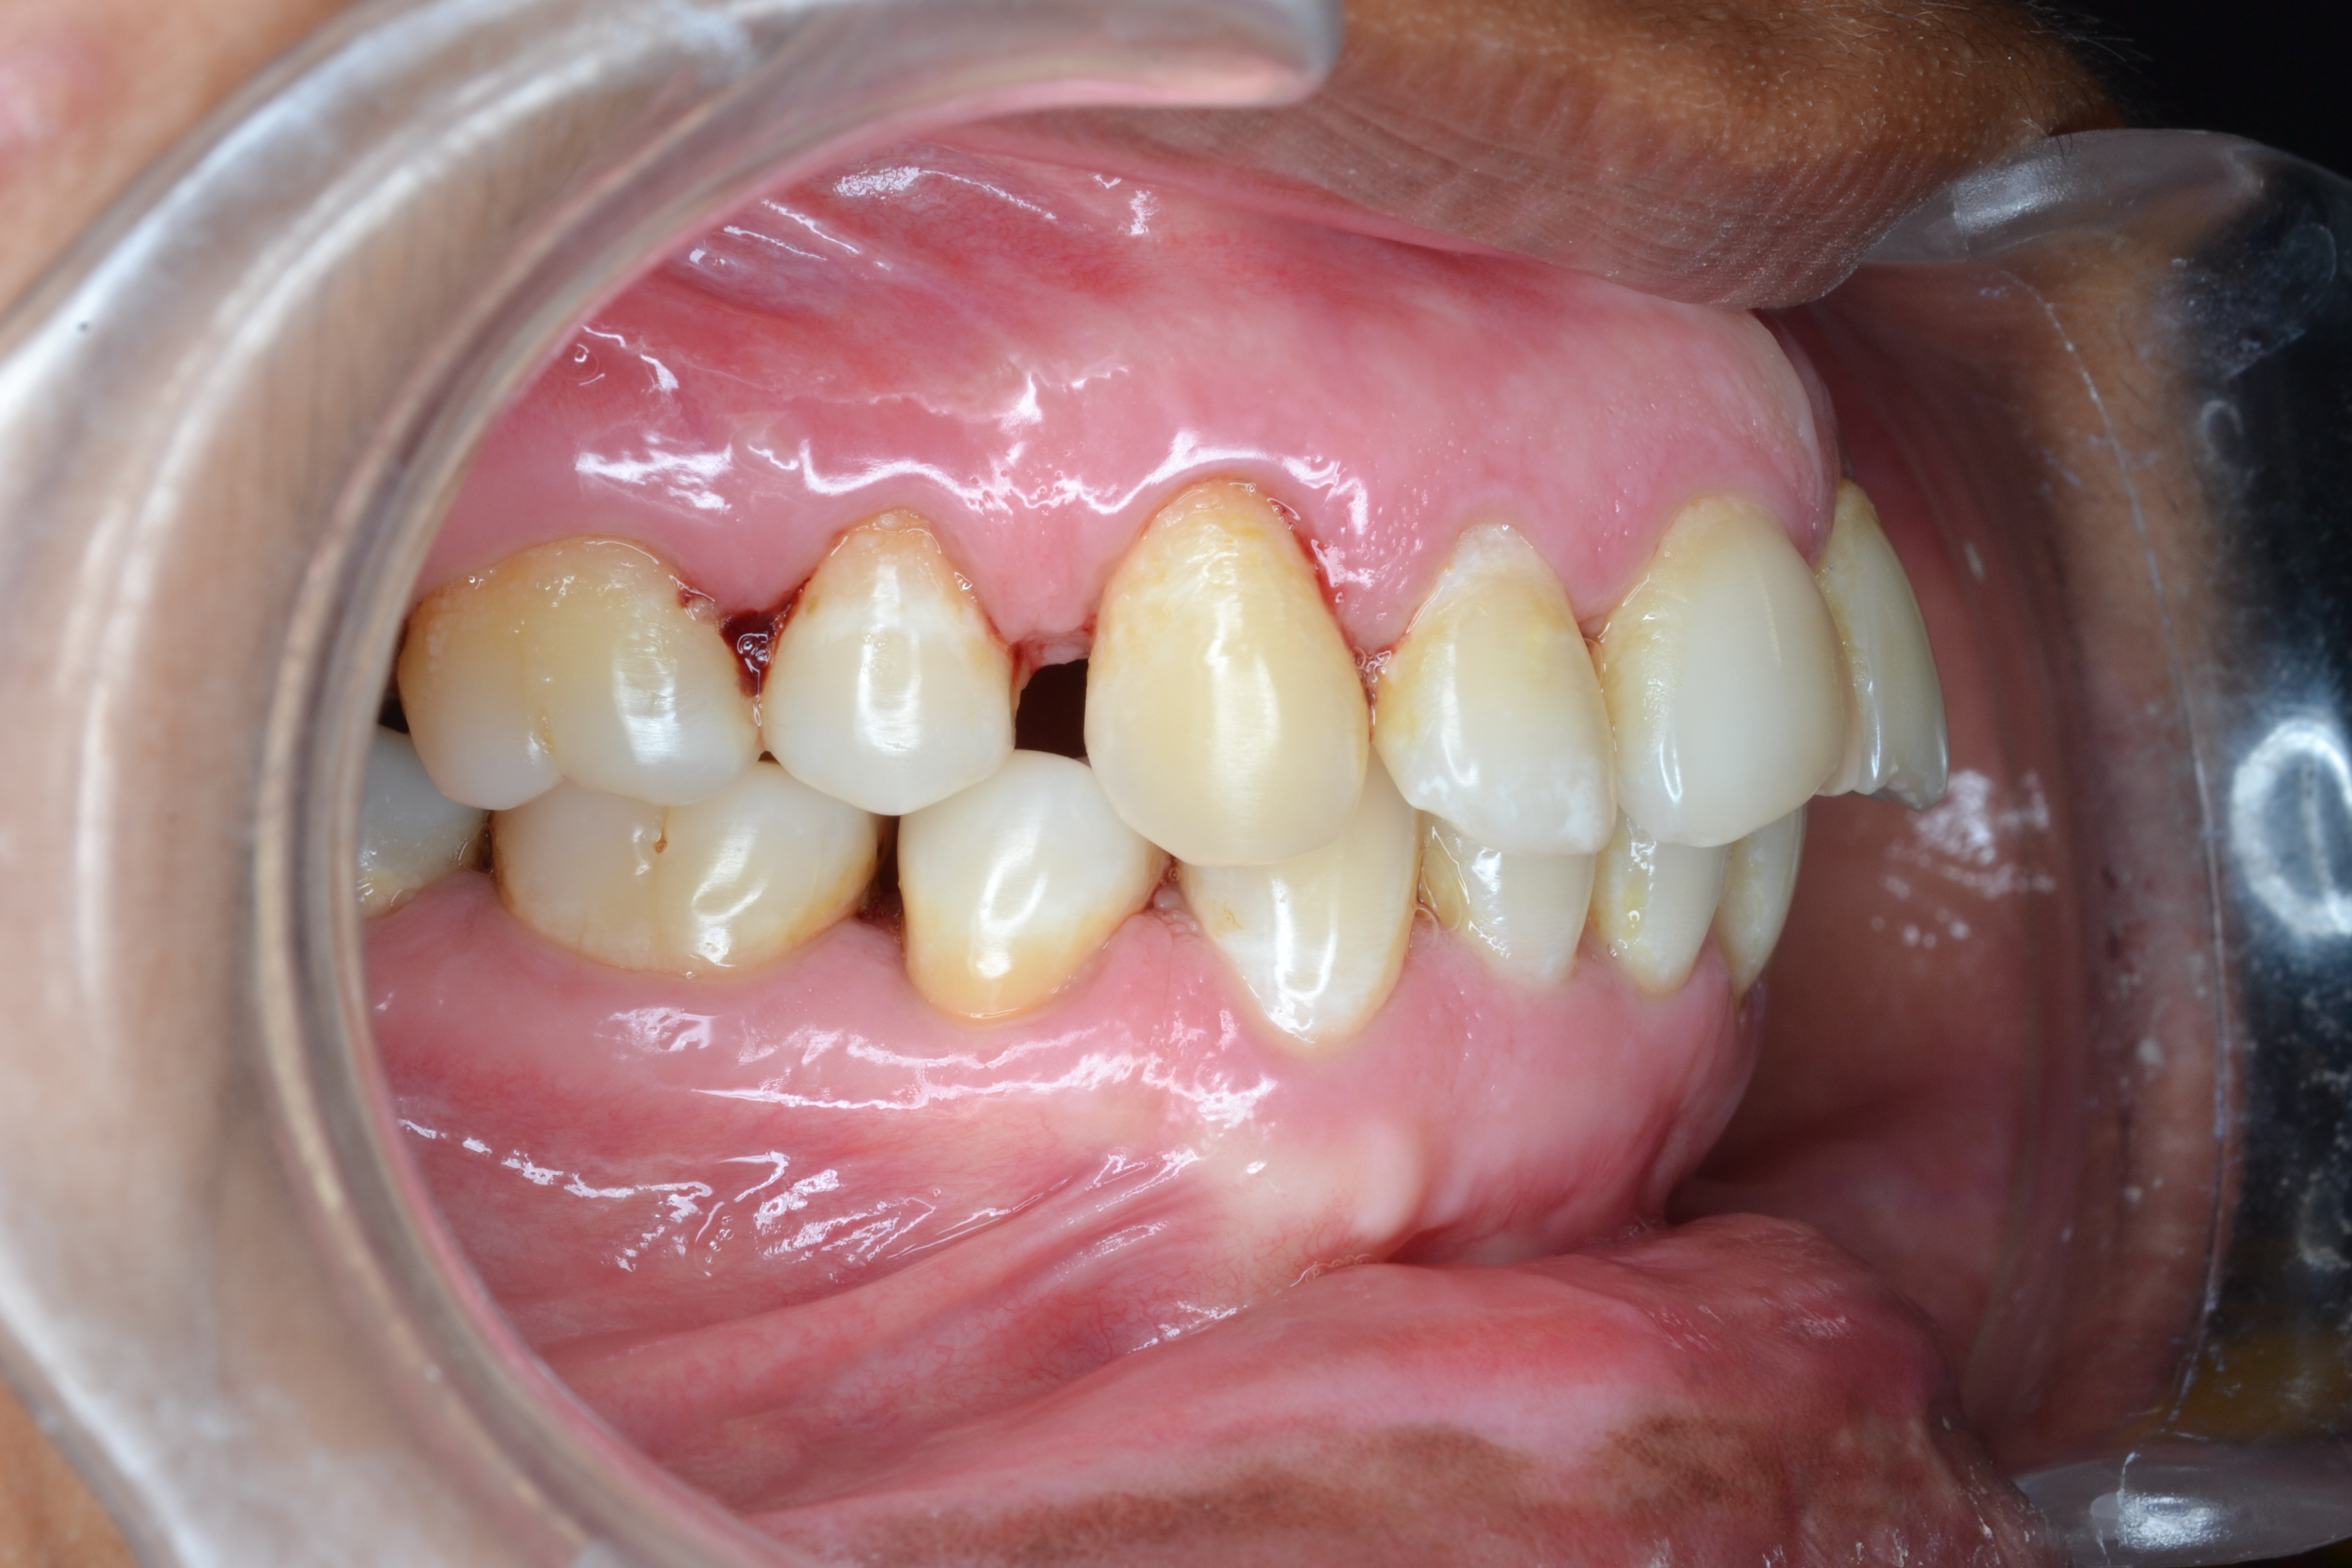

After/Before

See stunning smile transformation before and after

Before After